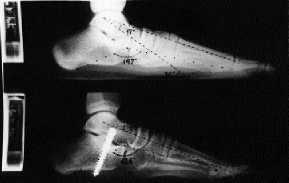

Este procedimiento se basa en la comprensión de la biomecánica del retropié, en la que se interrelacionan como diversos componentes de un mismo movimiento, tanto la flexión plantar, la adducción y la listesis anterior del astrágalo, así como la eversión del calcáneo.19 Todos ellos concurren a nivel de la articulación subastragalina de tal modo que si se frena uno se frenan todos (stop one, stop all).17 En la técnica de calcáneo-stop el tornillo colocado en el margen externo del seno del tarso, apoyándose contra la cara lateral del cuello del astrágalo justo anterior a la apófisis astragalina externa, se opone a la caída plantar, listesis con rotación interna del astrágalo e inclinación valguizante del calcáneo (Fig. 1). La corrección del antepié y arco interno serían secundarias al restablecimiento de la relación astrágalo-calcáneo. Esta corrección mantenida se estabiliza y mejora por la remodelación residual y el retensado espontáneo de las estructuras capsuloligamentosas.1

A

B

C

Figura 1. A: Esquema mostrando las acciones: antilistesis anterior-caída plantar del astrágalo (1), oposición a la inclinación valguizante del calcáneo (2) y a la rotación interna-caída plantar del astrágalo sobre el eje imaginario (3). Radiografías pre y postoperatorias de un niño de 13 años. En proyección AP (B) los ángulos astrágalo-calcáneo y astrágalo-escafoideo pasaron de 19 a 16° y de 59 a 66°, respectivamente. En proyección lateral (C) los ángulos astrágalo-metatarsiano, Costa-Bartani y flexión plantar del astrágalo pasaron de 17 a 0°, de 147 a 136° y de 36 a 22°, respectivamente.